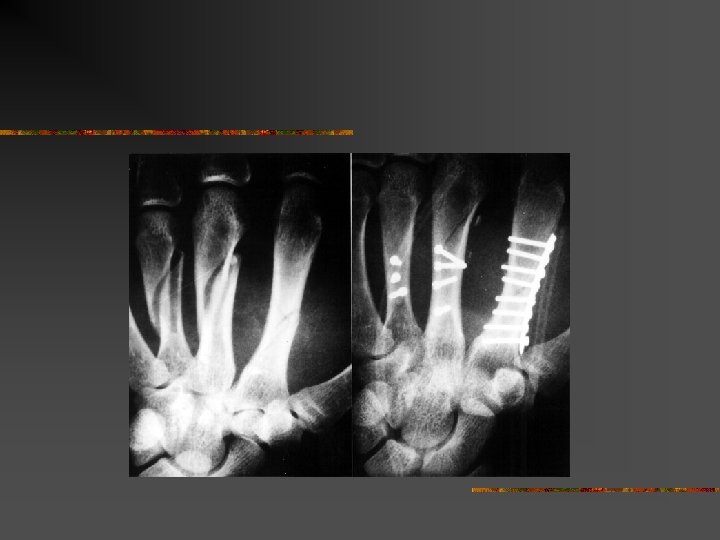

Traitement n Chirurgical : n n n Abord chirurgical de l’articulation Réduction sous contrôle de la vue Stabilisation par broche

Méthode de traitement n n n Mobilisation immédiate = Tt fonctionnel Traitement orthopédique = immobilisation Traitement chirurgical = n n n Broches Vis et plaques Fixateur externe

Indications : n n Traitement chirurgical : Le but : n n Montage solide pour mobilisation précoce Eviter les raideurs

Indications : n Quelles fractures opérer ? Fractures instables ouvertes ou fermées (Fractures qui se déplacent spontanément après réduction) n Fractures articulaires n